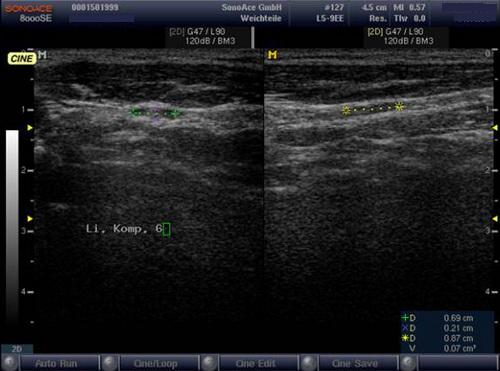

Sonografie: Sonographisch 3 suspekte Lymphknoten cervical rechts.

Sonografie: Kein Korrelat des Verdachts einer zervikalen Lymphknotenmetastase.